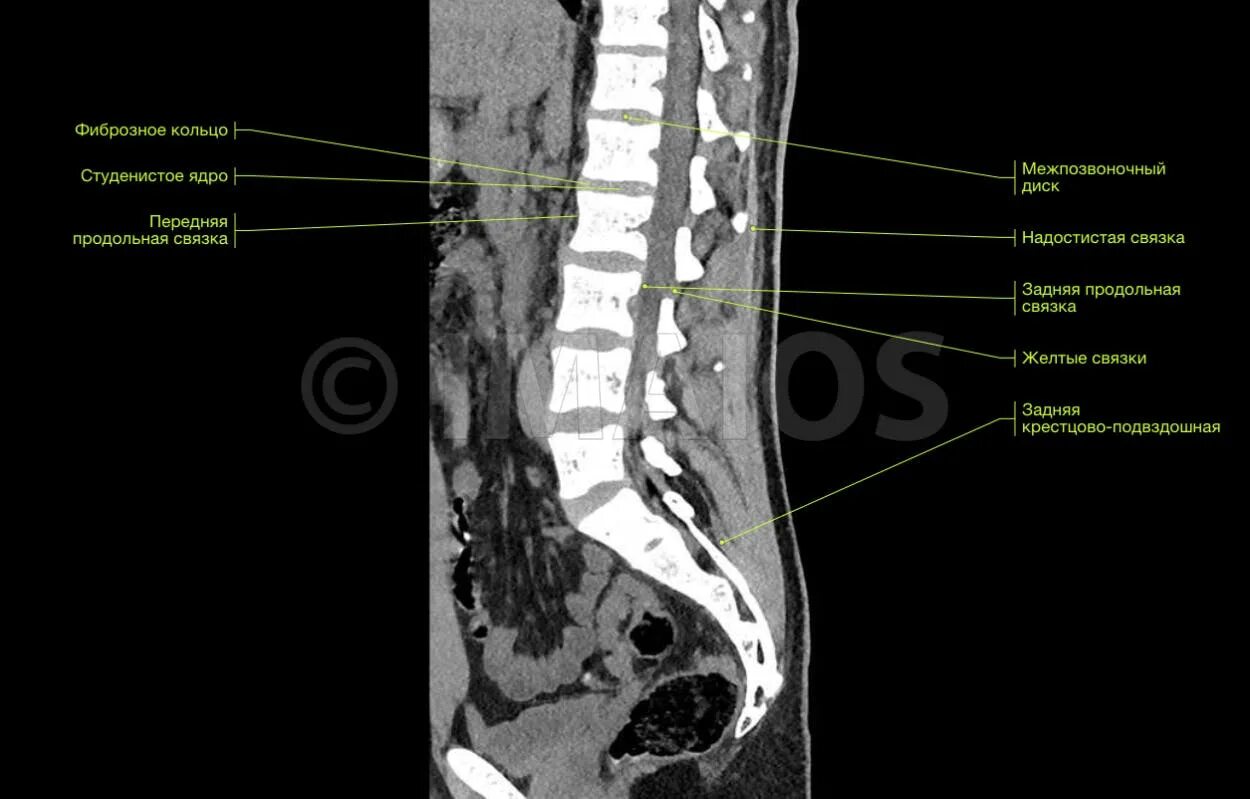

Как делают кт пояснично крестцового отдела